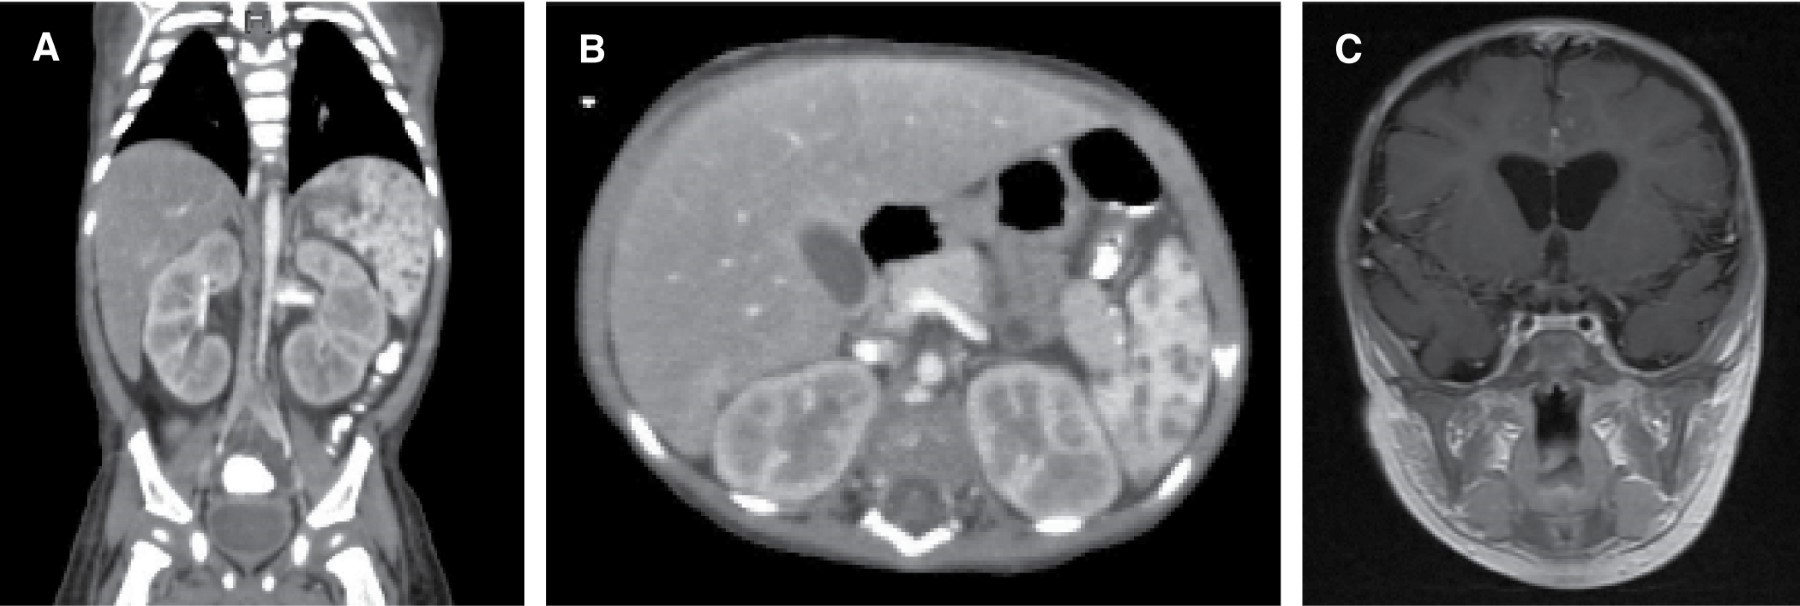

Figure 1